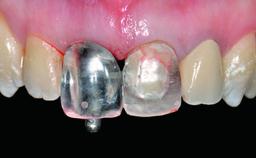

Replacement of a Failing Upper Left Central Incisor: Immediate Placement of an RC Bone Level Implant and Provisionalization

A healthy 23-year-old female patient was referred for a consultation on replacing tooth 21 with an implant-supported restoration. The patient had recently moved to the area and reported a history of endodontic and periodontal treatment for tooth 21. The tooth had been deemed non-restorable by her previous periodontist but since she was going to be moving, he recommended consulting to a dentist in her new city to continue her treatment. A review of her medical history yielded no significant findings and no known drug allergies. The analysis of her smile revealed a medium to high symmetrical smile line and a slightly discolored tooth 21.

Provisional Implant-Supported Prosthesis Prosthodontic margin < 3 mm apical to mucosal margin Prosthodontic margin < 3 mm apical to mucosal margin